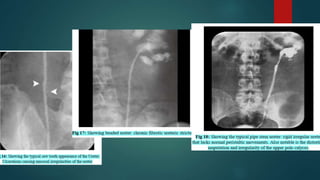

BARIUM

volvulus